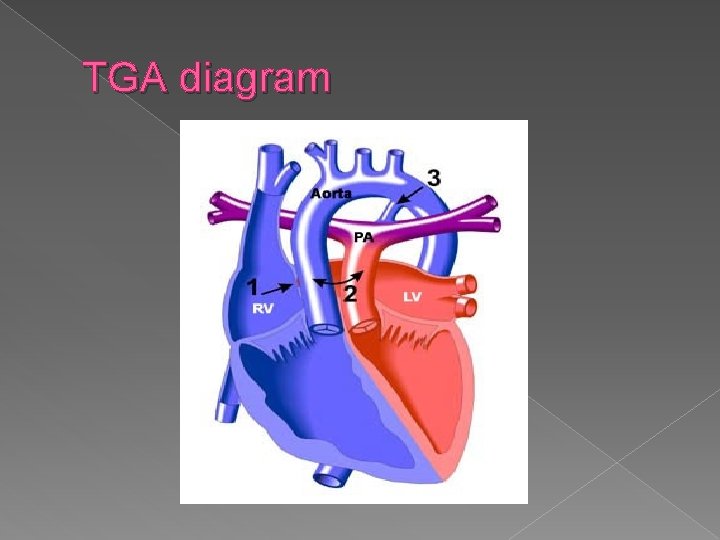

TGA diagram

Transportation of the Great Arteries (TGA) Once again, � The origin of the great vessels are transposed so that the aorta arises from the right ventricle (instead of the left ventricle) and the pulmonary trunk arises from the left ventricle ( instead of the right ventricle)